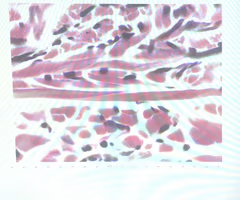

term image

intercalated discs- attachment sites between cardiac muscle cells